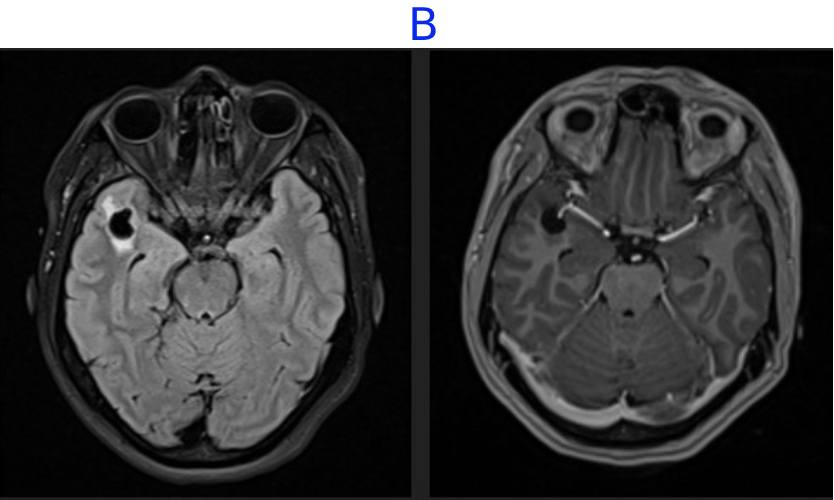

C. FINDINGS - MR BRAIN

• C. No diffusion restriction in DWI